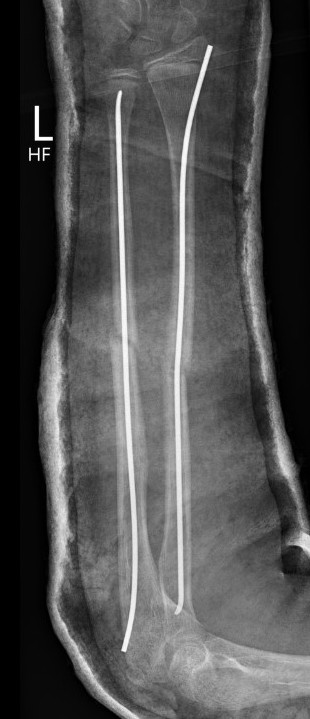

3. Intramedullary elastic nail

TENS technique

Technique

Radius (typically first as more difficult to reduce)

Entry point with awl 2 cm proximal to distal physis

1. Radial styloid / distal lateral entry

- ensure radial nerve / cephalic vein, 1st extensor compartment protected

2. Listers tubercle / dorsal entry

Elastic Nail size

60 - 70% of the intramedullary canal

Typically 1.5 - 2.5 mm

Fracture reduction

Avoid passing nails incorrectly multiple times as may cause compartment syndrome

Bend tip of elastic nail

May need small open reduction

Cut nail

Withdraw 1 cm, cut with endcutter, then advance

Ulna (usually reduced after radius fixation)

Entry point 2 cm distal to apophyseal plate

1. Proximal lateral

- avoids ulna nerve

3. Distal medial

Postoperative

Cast in supination to tighten interosseous membrane

Cast 6 weeks

Removal of TENS at 4 - 6 months once osseous union established